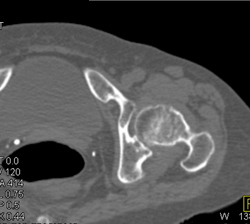

Talus Fracture